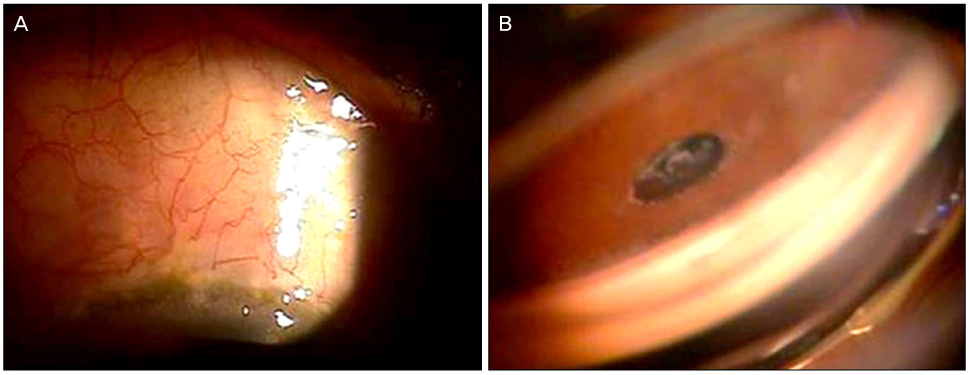

맥락막 삼출 (Suprachoroidal effusion)

맥락막 삼출이라는 것은 맥락막 혈관으로부터 삼출물들이 나오면서,

맥락막과 공막 사이의 공간인 “맥락막 상강, suprachoroidal space”에 고이는 것을 말합니다.

눈이 작은 소안구증( nanopthalmos) 나 Sturge-weber syndrome에서 흔히 동반되며,

갑작스럽게 맥락막 삼출이 발생하게되면, 이로 인해서 섬모체가 앞쪽으로 밀리면서,

수술도중 갑작스럽게 전방이 얕아지게됩니다.